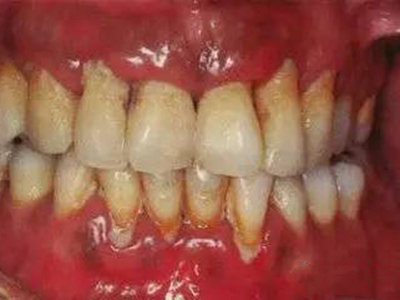

急性坏死性溃疡性龈炎起病急,病程短,常为数天至1-2周,以龈乳头和龈缘的坏死为其特征性损害,尤以下前牙多见,初起时龈乳头充血水肿,个别龈乳头顶端可发生坏死性溃疡,上覆有灰白色坏死物,中央凹下如火山口状。龈缘如虫蚀状,坏死区出现灰褐色假膜,擦去后可见出血创面。龈乳头被破坏后与龈缘成一直线,如刀切状。病损一般不波及附着龈,患处牙龈极易出血,疼痛明显并有腐败性口臭。

重症患者可有低热、疲乏等全身症状,并可伴有下颌下淋巴结肿大和压痛。有的患者可能进展为坏死性龈口炎、坏死性溃疡性牙周炎等疾病,从而导致牙周袋形成、牙槽骨吸收和牙齿松动。